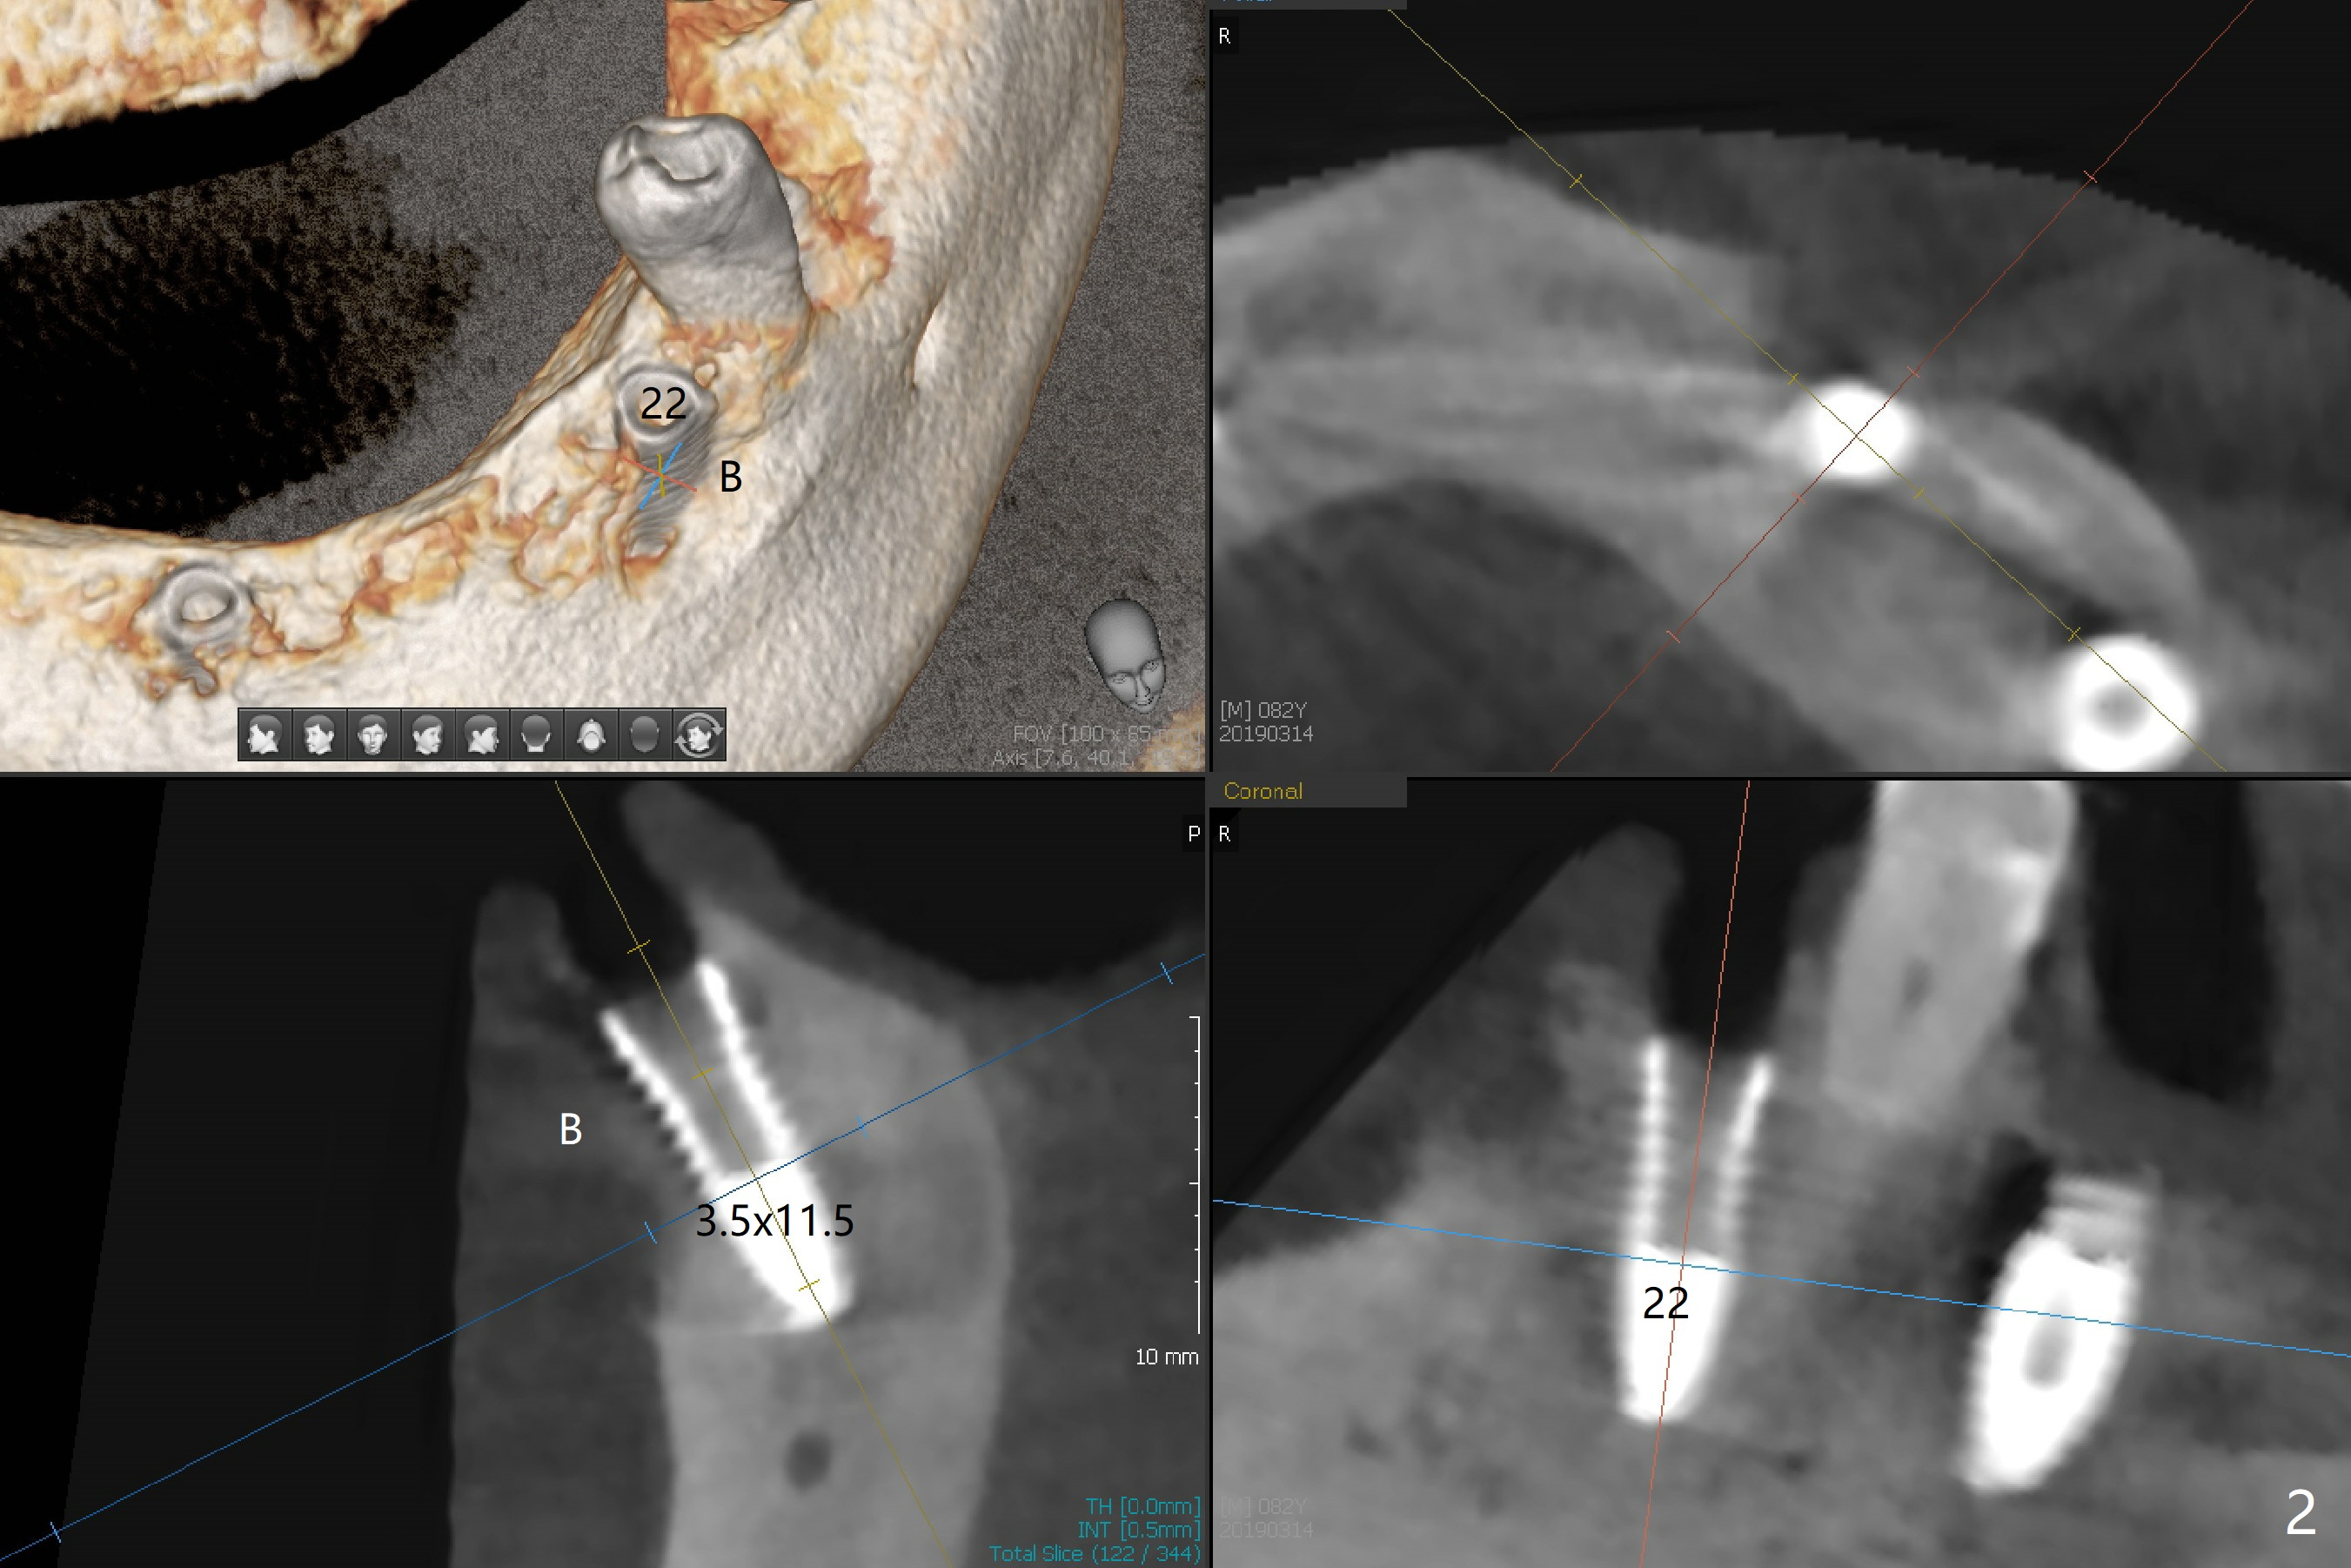

Three months post socket preservation (with buccal plate loss previously), a 3.5x11.5 mm implant is placed at #27 subcrestal (Fig.1). When implants are placed at #22 and 20 (Fig.2,4), threads are exposed buccal (B). Mixture of autogenous bone and allograft is placed to cover the exposed threads (Fig.3,5) following deep placement at #20. For safety, the implant at #20 is buried. Pain control at #18 is poor when initial osteotomy is being established (Fig.6 *), as related to severe infection. Repeated block anesthesia allows to finish implant placement with primary stability; a 3.5x2 mm ball abutment is placed (Fig.7). With placement of 2 other ball abutments at #27 and 22 (Fig.3), the lower existing RPD is converted to a removable provisional (Fig.8). With addition of acrylic, the socket of #20 is covered (Fig.9). There is no apparent bone #20 distal 3 months postop (Fig.10,11 <). Re-graft is needed? The implant at #21 appears immediately subgingival 5 months postop (Fig.12 *). The distobuccal threads are exposed (Fig.13). After decortication, allograft is placed, followed by 6-month membrane. In fact, a shorter and smaller implant should be placed instead. The patient has to wear the RPD for mastication. It would be more painful without it. Later the tissue surface of the RPD is trimmed.